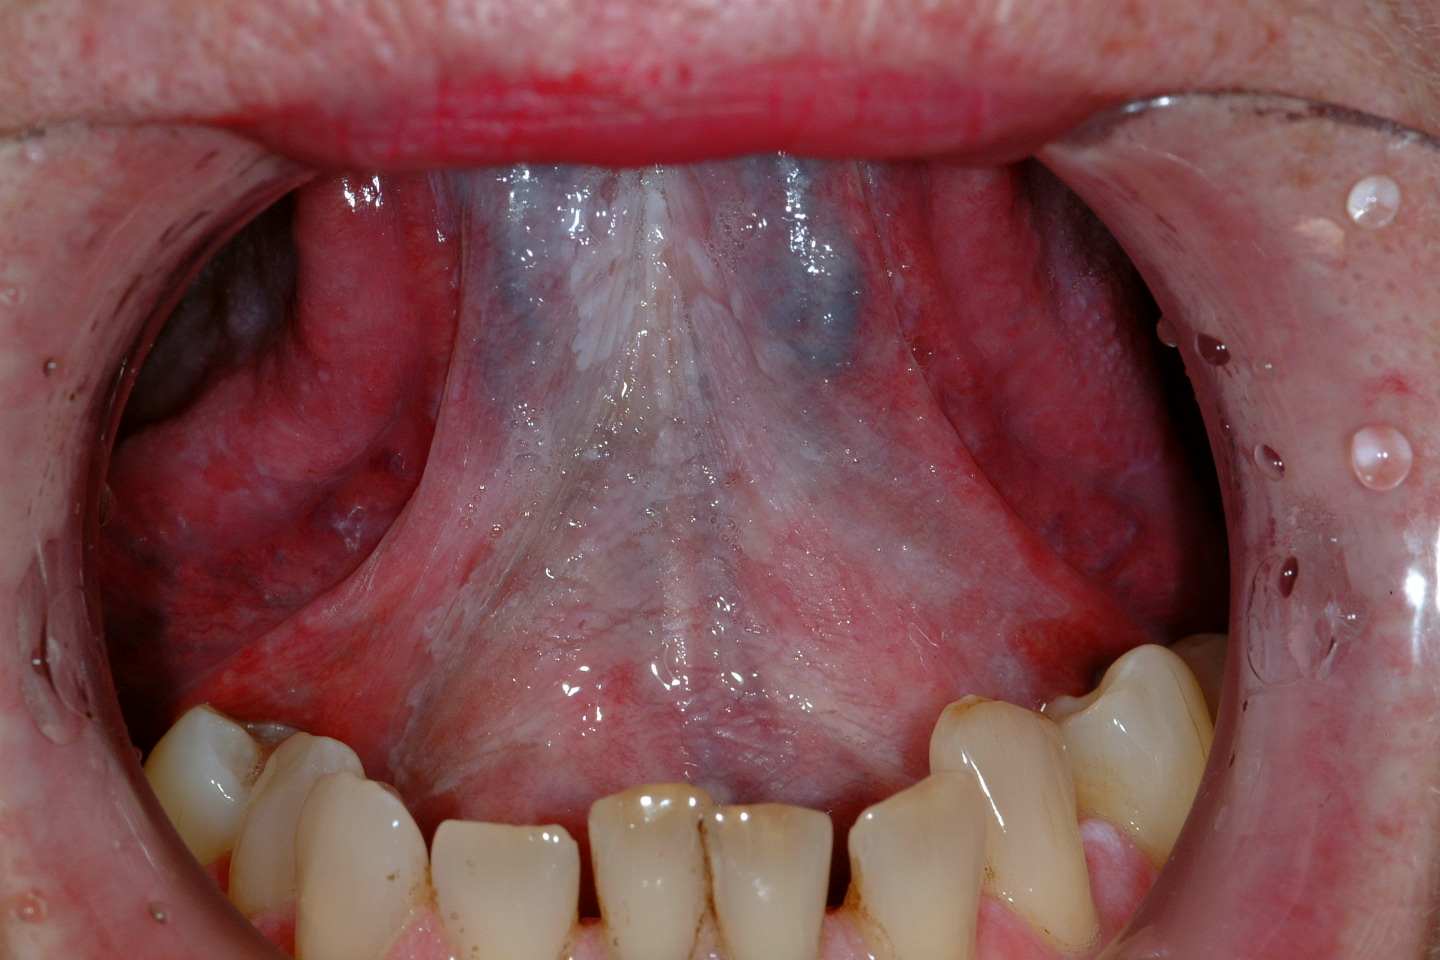

Oral leukoplakia (according to the World Health Organisation definition) is a white patch or plaque that cannot be characterised, clinically or histopathologically, as any other disease. There are a number of possible causes for white patch oral mucosal lesions and similar looking such lesions are quite common. Leukoplakic patches can appear in all areas of the mouth but the side of the tongue and the floor of the mouth (see Figure 1) are common locations. Leukoplakic patches come in a range of appearances and may be completely asymptomatic or cause symptoms. The overall risk for leukoplakic patches to become malignant has been quoted as 2 to 8 %.